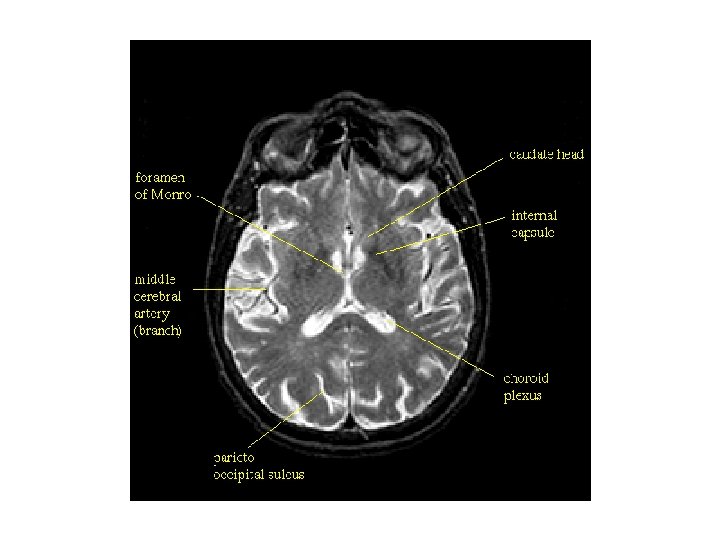

뇌실계(ventricular system)의 구조 1. 전두각(frontal horn, 전각 anterior horn) 3. 측면삼각(collateral trigone, 외측뇌실방 atrium) 5. 측두각(temporal horn, 하각 inferior horn) 2. 중심부분(central portion, body) 7. 제 3뇌실(3 rd ventricle) 4. 후두각(occipital horn, 후각 posterior horn) 6. 몬로공(formanen of Monro, 뇌실간공 intervertebral foramen) 8. 중뇌수도관(cerebral aqueduct, 대뇌수도) 9. 제 4뇌실(4 th ventricle) 10. 시상간접합부(interthalamic adhesion, 시상간교) 11. 시각상오목(supraoptic recess, 시삭상와) 13. 송과선상오목(suprapineal recess, 송과상 와) 15. 외측오목(lateral recess, 외측와) 12. 깔때기오목(infundibular recess, 누두와) 14. 송과선오목(pineal recess, 송과체와)